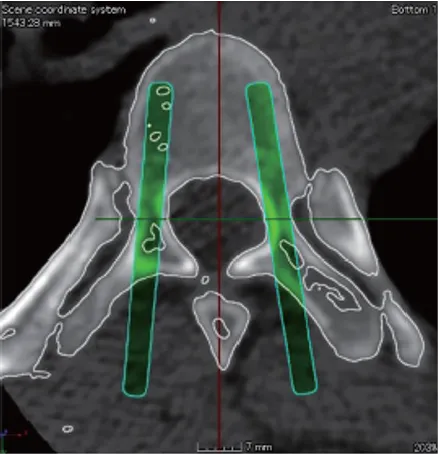

SpineMate Ti Guide

2024年に薬事承認を取得した椎弓根スクリューを正確に刺入するための患者適合型ガイドです。患者さま個々の骨形状に合わせて作成します。